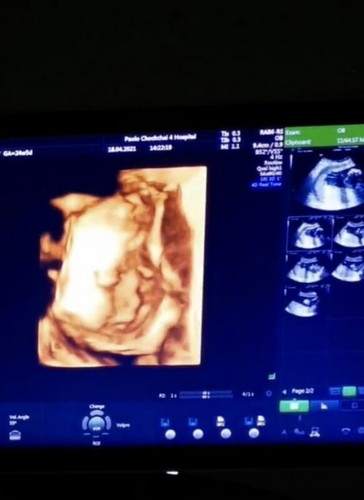

26วีค ซาวน์4มิติ

พบเด็กอ้วน 1 อัตราค่าาา 26 วีค แล้วลุงหมอบอกว่า นน. เกินอายุครรภ์แล้วน้า แม่บำรุงเยอะไปหน่อย หนูกลายเป็นคนอ้วนสองต่อจากแม่แล้ว 😅😅 ขอให้หนูเป็นเด็กดีนะคะ แข็งแรงโตไวไว แก้มป่องแบบแม่เลยยย #แกมมี่ #หนูเป็นเด็กผู้หญิงค่ะ

ทีมลูกสาวเหมือนกันค่ะ 25 สัปดาห์ น้ำหนัก 883 🥰